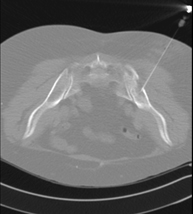

Prova que consisteix en obtenir una mostra de teixit de lesions toràciques, com per exemple masses pulmonars, mediastíniques, lesions òssies, etc. Per això s'administra anestèsia local sobre la zona de punció, que es realitza amb agulles de calibre fi. Tot el procediment es realitza controlat amb imatges obtingudes per tomografia computaritzada (TC) en diversos moments de la punció, mitjançant un equip de Fluoroscòpia-TC. Després de la prova, el pacient resta unes hores hospitalitzat. És necessari portar proves de coagulació abans de la punció. - Biòpsia tòrax guiada per TC

Consisteix en obtenir una mostra de teixit d'una determinada lesió toràcica, com per exemple del pulmó, del mediastí, de l'estern, etc. A vegades es realitza sota sedació, amb l'ajuda de l'equip d'anestèsia. S'utilitzen agulles que permeten l'obtenció d'un cilindre de la lesió a estudiar que s'enviarà a Anatomia Patològica per a la seva anàlisi histològica. Tot el procediment es realitza controlat amb imatges obtingudes per tomografia computaritzada (TC) en diversos moments de la biòpsia, mitjançant un equip de Fluoroscòpia-TC. Després de la prova, el pacient resta hospitalitzat per controlar la seva evolució. És necessari portar proves de coagulació abans de la punció. - TC Columna Dorsal

Prova que consisteix en obtenir una mostra de teixit de lesions toràciques, com per exemple masses pulmonars, mediastíniques, lesions òssies, etc. Per a tal s'administra anestèsia local sobre la zona de punció, que es realitza amb agulles de calibre fi. Tot el procediment es realitza controlat per imatges obtingudes per Tomografia Computaritzada (TC) en diversos moments de la punció mitjançant l'ús de Fluoroscòpia- TC. Després de la prova, el pacient resta unes hores hospitalitzat. És necessari que porti les proves de coagulació abans de la punció. - Biòpsia de tòrax guiada per TC

Consisteix en obtenir una mostra de teixit d'una determinada lesió toràcica, com per exemple del pulmó, del mediastí, de l'estern, etc. A vegades es realitza sota sedació, amb l'ajuda de l'equip d'anestèsia. S'utilitzen agulles que permeten l'obtenció d'un cilindre de la lesió que s'ha d'estudiar, que s'enviarà a Anatomia Patològica per a la seva anàlisi histològica. Tot el procediment es realitza controlat per imatges obtingudes per Tomografia Computaritzada (TC) en diversos moments de la biòpsia mitjançant l'ús de Fluoroscòpia-TC. Després de la prova, el pacient resta hospitalitzat per controlar la seva evolució. És necessari que porti proves de coagulació abans de la punció. - PAAF (Punció) abdominal guiada per TC